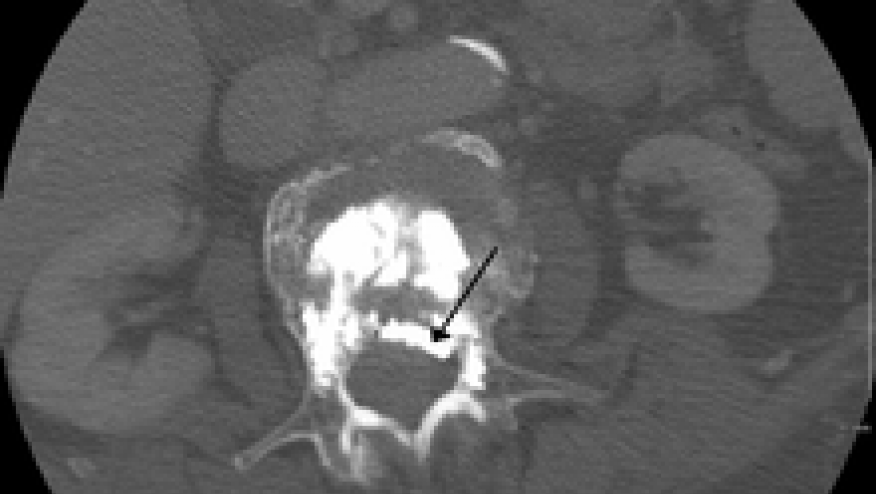

There are approximately 750,000 new vertebral compression fractures each year in the United States, with resultant acute and chronic back pain in over one‐third of patients with vertebral fractures (VF). Both percutaneous vertebroplasty or balloon kyphoplasty have been advocated as useful means of restoring vertebral height and strength capable of reducing pain in symptomatic patients. Balloon kyphoplasty is currently more expensive and is performed almost three times more commonly than percutaneous vertebroplasty in the United States